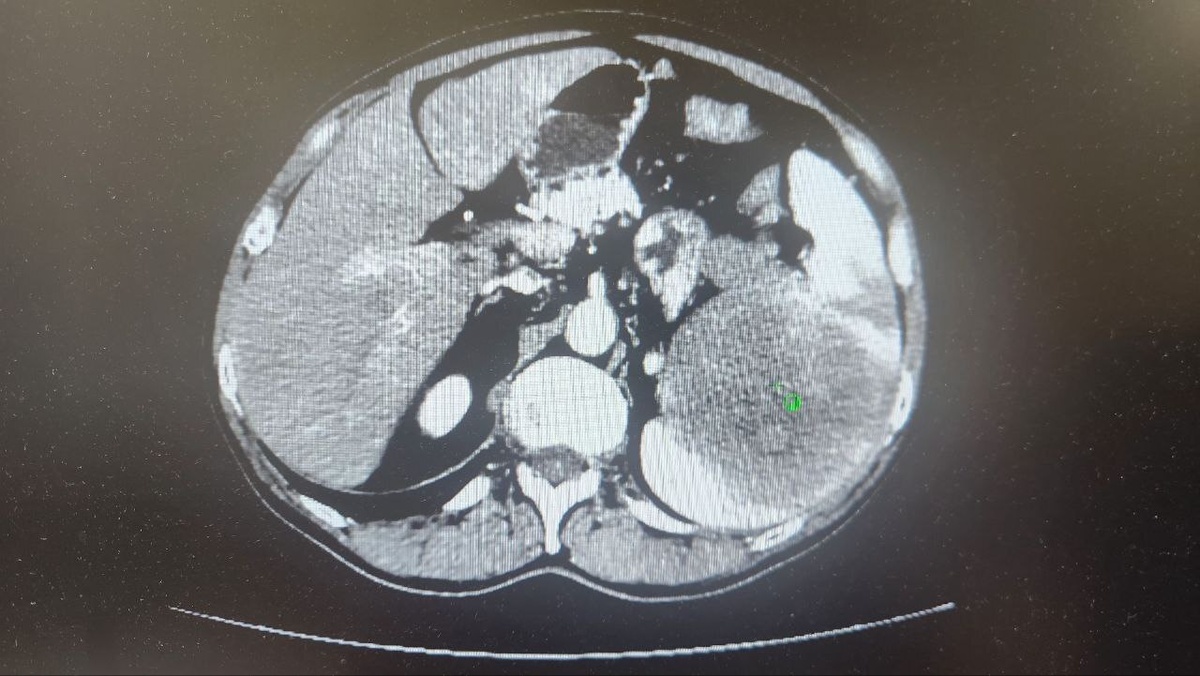

В Тульском областном клиническом онкологическом диспансере онкохирурги успешно удалили опухоль селезенки 25×20 см. Современный метод минимизировал травму для пациента и ускорил восстановление.

Опухоль нашли у 69-летнего туляка на плановом УЗИ брюшной полости. Дальнейшее обследование подтвердило диагноз: опухоль поразила селезенку, лимфоузлы и хвост поджелудочной железы.

Врачи приняли решение об удалении единым блоком селезенки, части поджелудочной железы с опухолью и пораженными лимфоузлами с использованием лапароскопического метода.